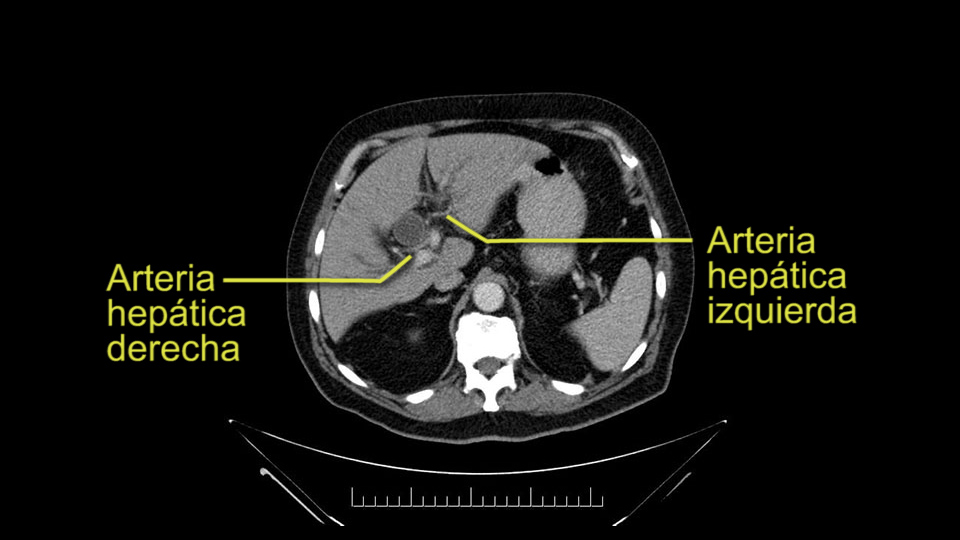

Then you look for anomalies. The one you worry about the most doing a Whipple is a replaced or aberrant right hepatic artery coming off the SMA at its origin. So again, find the SMA. You can find it because the renal vein goes through it. Follow it up, up-up-up. Nothing coming off of there that I can see here. Nothing coming off of it, nothing coming off of it and just to confirm it, look at the celiac trfurcation. There’s the celiac, there’s the bifurcation, there's the splenic artery, hepatic artery. Make sure there’s a right, which there is here. The right usually goes under the bile duct: important when you’re going around the bile duct to do a Whipple. A replaced right goes under the portal vein and the bile duct way over here on the right. That’s about it.

The other slowing down moment would be the gastroduodenal artery. Confirming that the gastroduodenal artery is not a dominant artery supplying blood to the liver. Liver failure is something which we don’t want due to altered blood supply to the liver or hampered arterial blood supply to the liver. So I would dissect out the hepatic artery, the left and right branches very clearly. Put a bulldog clamp on the gastroduodenal artery, make sure that the perfusion of the liver is excellent on the right and left side, and then divide the gastroduodenal artery. I would avoid using crushing instruments or crushing clamps on the gastroduodenal artery because they have a tendency to shatter in patients who are old with friable vessels so you have to be careful and tackle it with the help of a 5-0 or a 6-0 prolene sutures. In younger patients, I would just apply clips and move on when it comes to dividing the gastroduodenal artery.

To plan a pancreatoduodenectomy, we start by reviewing the vascular anatomy, especially the origin of the celiac trunk, here, in front of the aorta, looking for any evidence of stenosis. In addition, we look at the origin of the superior mesenteric artery, to look for any branches, and any replaced right hepatic arteries coming from the superior mesenteric artery; which does occur in about 12% of the population.

The second point about the vascular anatomy-, is to again look for right hepatic arteries in the hilum, coming from the superior mesenteric artery by palpating-through the Winslow Hiatus. Usually we will check for a pulse in the posterior aspect of the hepatic hilum, where a right hepatic artery should not usually be found. In this case, the precaution is to avoid an accidental ligation of the right hepatic artery that might jeopardize perfusion of the right lobe, or if there is a completely replaced hepatic artery that can put the liver circulation at risk.

Para planear una pancreatoduodenectomía, se debe revisar la anatomía vascular, especialmente el origen del tronco celíaco, aquí, por delante de la aorta, buscando areas de estenosis y por otro lado, el origen de la arteria mesentérica superior, para evaluar -sobre todo- si hay ramas, arterias hepáticas derechas provenientes de la mesentérica superior; lo cual ocurre en alrededor del 12% de la población.

E l segundo punto de la anatomía vascular, es nuevamente buscar arterias hepáticas derechas, en el hilio, provenientes de la mesentérica superior y eso lo hacemos palpando -a través del Hiato de Winslow- el hilio hepático y usualmente sentiremos un pulso en el aspecto posterior del hilio hepático, donde no debe ir el recorrido usual de la rama derecha de la arteria hepática. En este caso, la precaución es no realizar una ligadura accidental de la arteria hepática derecha y poner en riesgo -posiblemente- la perfusión del lóbulo derecho, o aún esta arteria puede reemplazar completamente la arteria hepática y poner en riesgo la circulación del hígado.